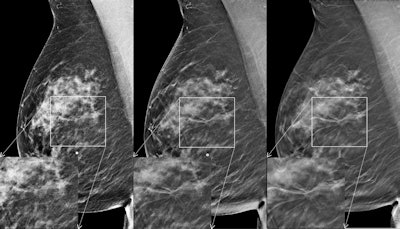

Craniocaudal images in 57-year-old woman with 8-mm invasive ductal carcinoma in the left breast. Left: FFDM image; middle: initial synthesized 2D image; right: DBT image. The region of interest is magnified for each image. Reader scores were 1 for FFDM, 3 for FFDM plus DBT, and 4 for synthesized 2D images plus DBT. This case was from study period 1. All images courtesy of RSNA.